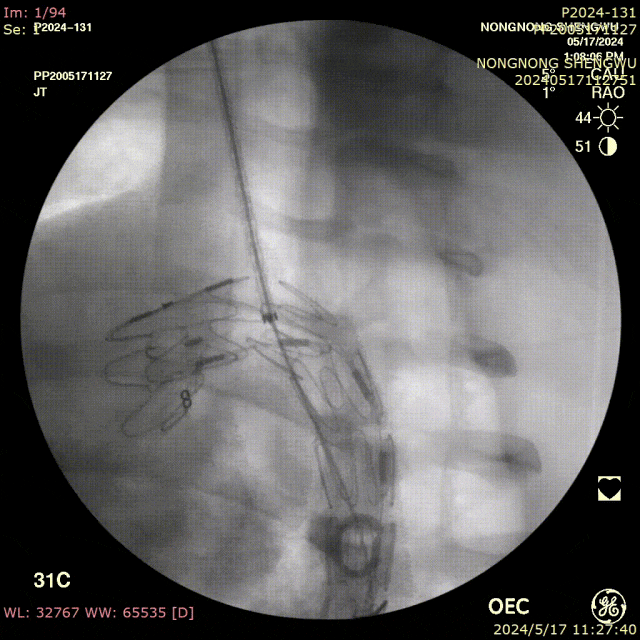

我们在两头35kg巴马公猪中完成动物实验:

成功实现弓上分支的快速、准确原位开窗;

破膜过程流畅,无分支或主动脉损伤;

取出标本可见圆形破口、支架贴合良好,证实技术可行性。

动物实验

巴马公猪35kg

标本